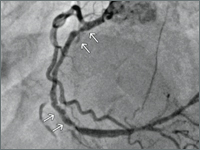

Hemofiltration in patient with cardio-renal syndrome type 2 in the course of preparation for revascularization procedure

SurgeryRenal failure occurs in about one-third of patients with acute heart failure and in about 25-40% of patients with chronic heart failure. Damage to one of these organs can secondarily lead to abnormal function of the other, which underlies the pathophysiology of CRS cardiac-renal syndrome.